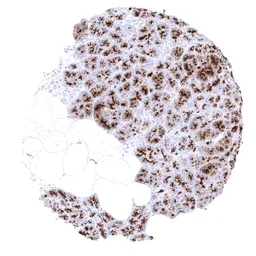

IHC-P analysis of human epithelioid malignant mesothelioma tissue using GTX04397 MUC1 antibody [MSVA-672R] HistoMAX™.

Malignant mesothelioma epitheloid variant with strong predominantly membranous MUC1 immunostaining of tumor cells.